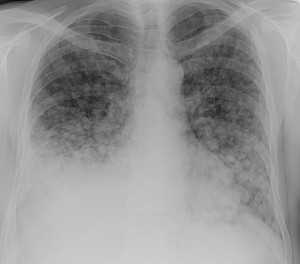

Гематогенные метастазы саркомы мягких тканей бедра на КТ (справа) и рентгенограмме (слева).